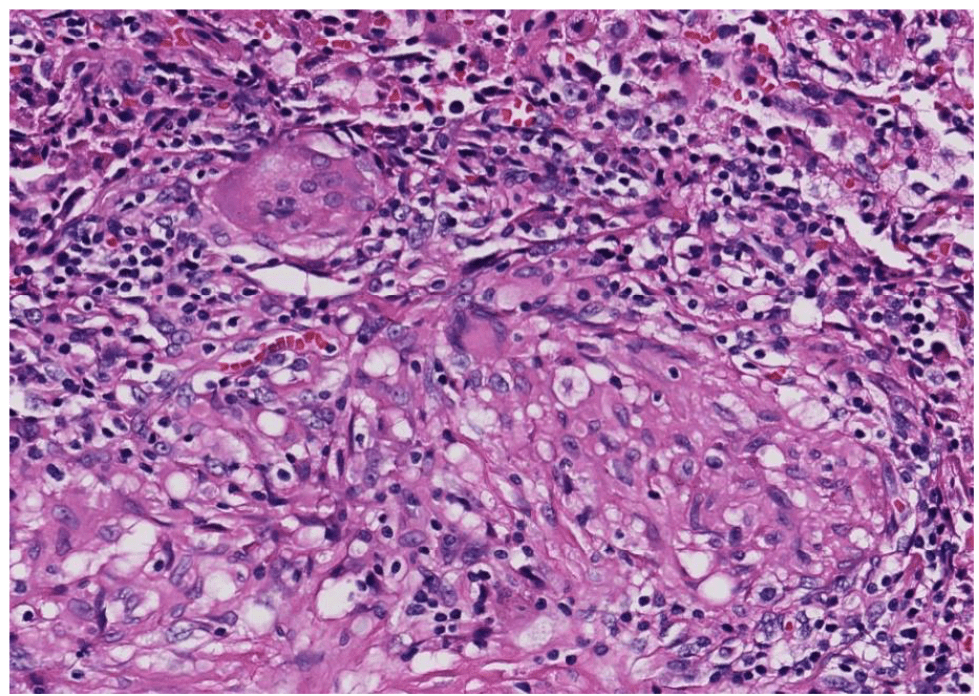

lung adenocarcinoma

colon cancer

endometrial cancer